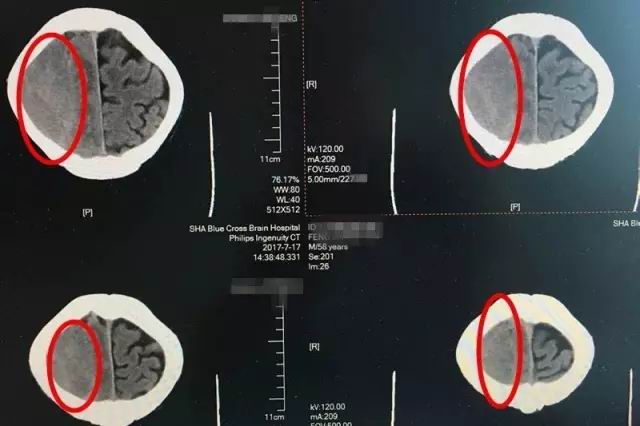

即便如此,时间不等人,等到七月中旬老冯一家辗转打听到上海蓝十字脑科医院,慕名找到神经内科的李振并主任时,老冯的症状已经开始加重了。入院时的脑CT影像检查显示,患者出血量增加,脑中线明显移位变质,左侧肢肌力3级(在和地心引力相反的方向中尚能完成其动作,但不能对抗外加的阻力),而且,他开始出现嗜睡、不思饮食的情况,如果再不及时治疗,患者很可能会陷入昏迷、偏瘫、失语、癫痫,巨大的风险正一步一步靠近。因此,迅速制定合理的治疗方案,才能及时挽救患者。

患者术前CT影像显示:红圈处为脑出血部位,出血量较大,颅内压升高